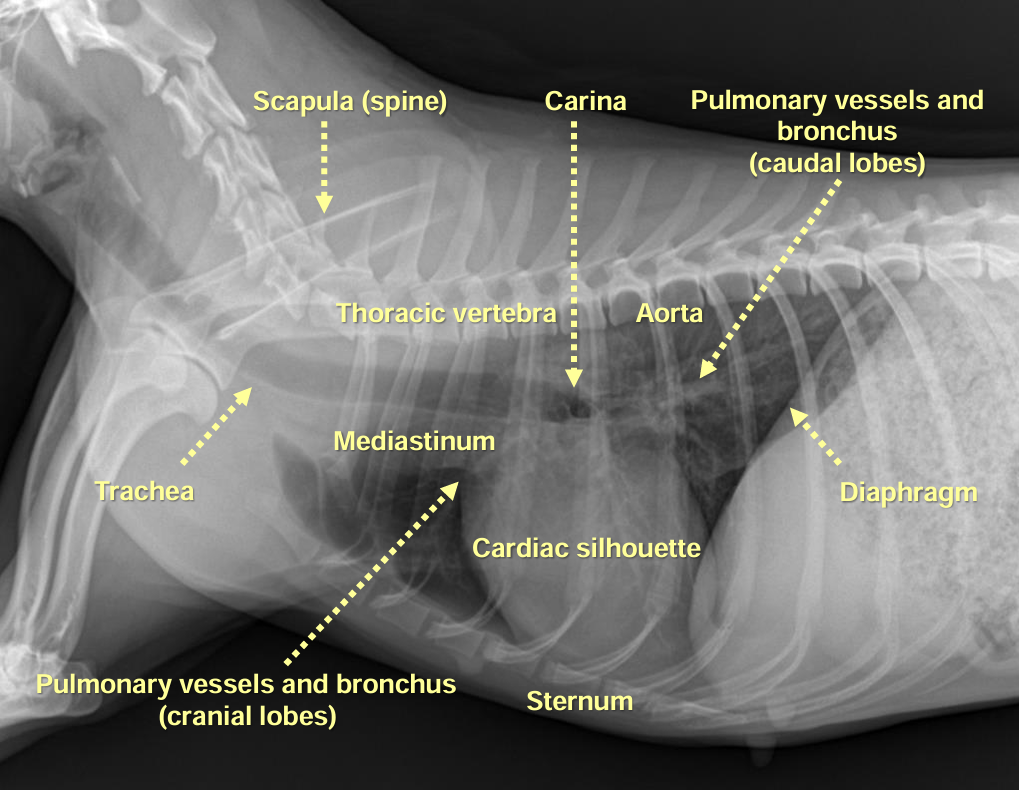

1. Normal Anatomy

| 정상적인 공기의 흐름 : Trachea - Bronchus - Bronchioles - Lung |